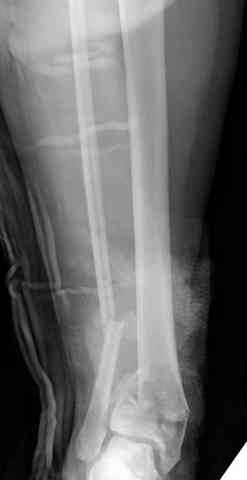

Яков изложил все необходимые аспекты лечения переломов пилона, и, не желая менять тему, решил выставить нашу точку зрения в двух клинических примерах.

При лечении внутрисуставных переломов типа "Pilon"

или "Tibial Plateau" на голени, применение простых

наружных фиксаторов типа "Spanning ExFix" или "Travelling ExFix" стал одним из стандартом этапного лечения.

Здесь выставлена пара случаев перелома пилона, оба

случая леченные этапным наружным фиксатором.

Второй случай фиксирован аппаратом Илизарова.